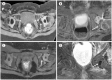

Developmental dysplasia of the hip is a condition characterized by hip joint instability due to acetabular dysplasia in infancy, necessitating precise ultrasound examination. Legg-Calvé-Perthes disease is caused by a temporary disruption in blood flow to the femoral head during childhood, progressing through avascular, fragmentation, re-ossification, and residual stages. Slipped capital femoral epiphysis is a condition where the femoral head shifts medially along the epiphyseal line during adolescence due to stress, such as weight-bearing. Differentiating between transient hip synovitis and septic arthritis may require joint fluid aspiration. Osteomyelitis can be associated with soft tissue edema and osteolysis. When multiple lesions are present, it is essential to distinguish between Langerhans cell histiocytosis and metastatic neuroblastoma. This review will introduce imaging techniques and typical findings for these conditions.